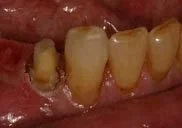

Before Crown Lengthening

This tooth required crown lengthening to provide enough tooth surface for a restoration